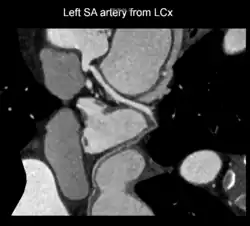

A left S-shaped sinoatrial artery, originating from the proximal left circumflex or LCx artery, has been described as a common variant in approximately 10% of human hearts.[5] This artery is larger than normal and supplies a good part of the left atrium, but also right-sided structures like part of the sinoatrial node and the atrioventricular nodal areas. In this variant, the artery courses in the sulcus between the left superior pulmonary vein and the left atrial appendage where it could be susceptible to injury during catheter or surgical ablation procedures on the left atrium, especially for atrial fibrillation ablation or open-heart cardiac surgery.